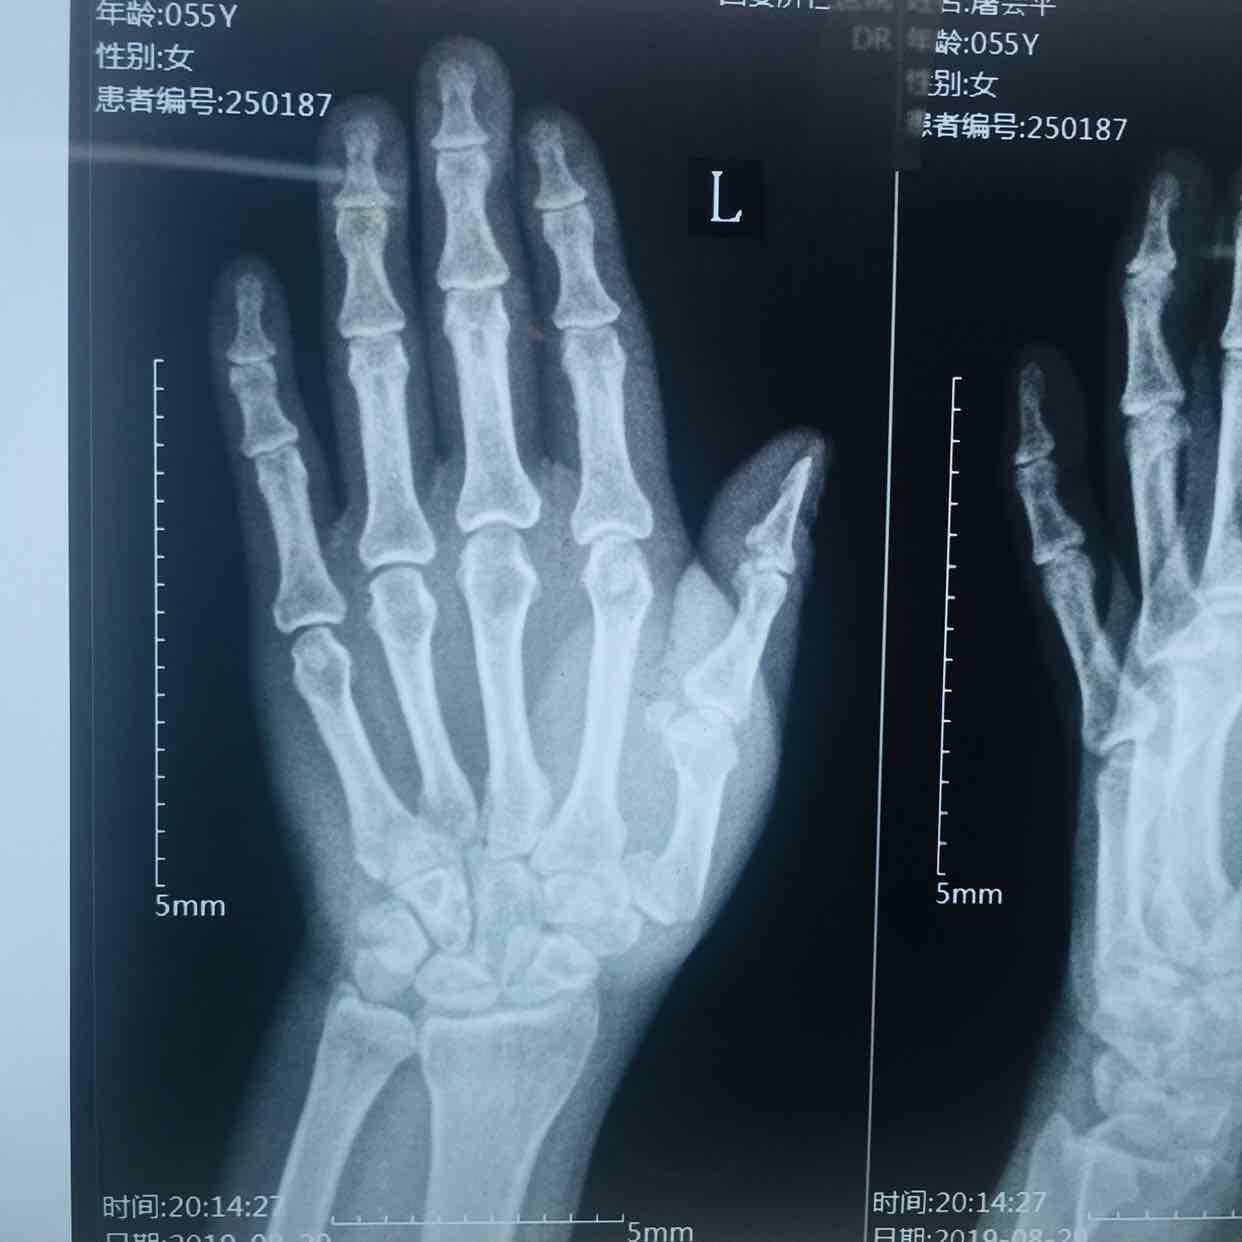

第一掌骨基底部骨折(微钢板固定)

生命体征平稳,心肺复未见异常。左手部肿胀明显,局部皮色发红,皮温高,压痛及纵向叩击痛阳性,第一掌指关节活动受限,末梢血运感觉正常。

诊断左手第一掌骨基底部骨折在臂丛麻醉下行切复内固定术,术后抗炎消肿等处理,石膏托外固定。